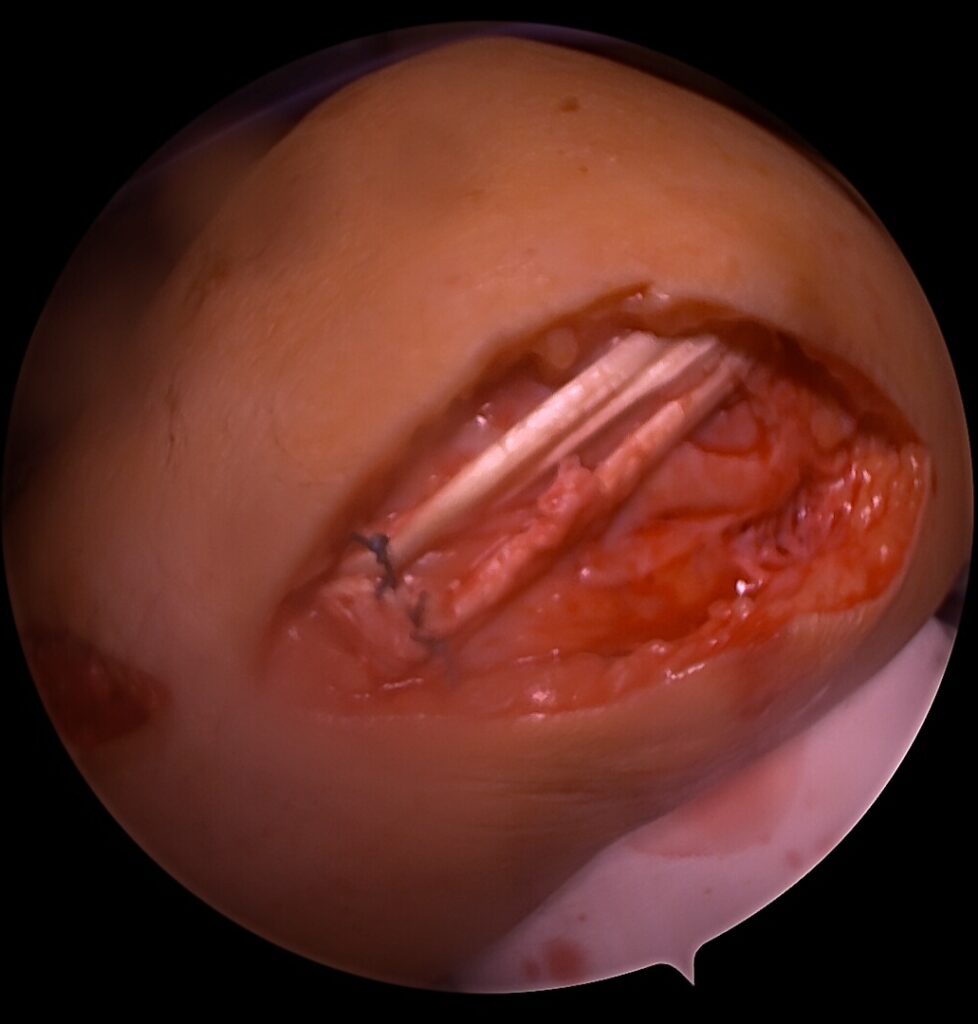

Kodėl V formos rekonstrukcija?

anatomiškai atkuria dvi funkcines kelio stabilumo kryptis

✔️ geriau paskirsto apkrovas

✔️ mažina likutinio nestabilumo riziką

Ši technika ypač svarbi po blauzdos kaulų išnirimo, kai pažeidžiamos kelios vidinės struktūros vienu metu.